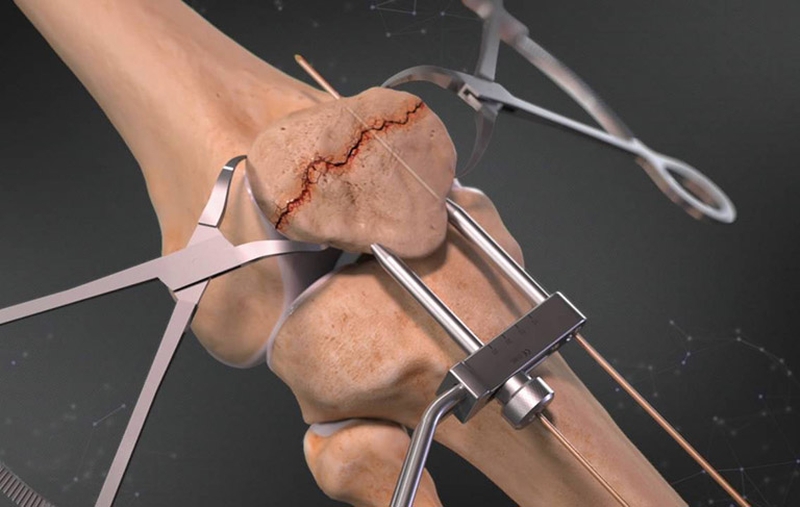

Điều trị phẫu thuật được chỉ định khi độ di lệch lớn hơn 4 mm và hoặc là trật khớp lớn hơn 2mm cũng như kèm theo hạn chế duỗi gối. Mục tiêu của việc điều trị phẫu thuật chính là sự thu nhỏ về mặt giải phẫu của bề mặt khớp cũng như tạo ra sự ổn định. Từ đó cho phép bệnh nhân có thể cử động sớm hơn và khôi phục chức năng đầu gối nhanh hơn.

Vậy thì gãy xương bánh chè có phải mổ không? Câu trả lời chính là tùy từng trường hợp. Cụ thể, đối với chấn thương không di lệch thì việc phẫu thuật là không cần thiết. Còn chấn thương có di lệch, theo tình trạng cụ thể sẽ có những cách xử lý như sau:

Phẫu thuật xương bánh chè